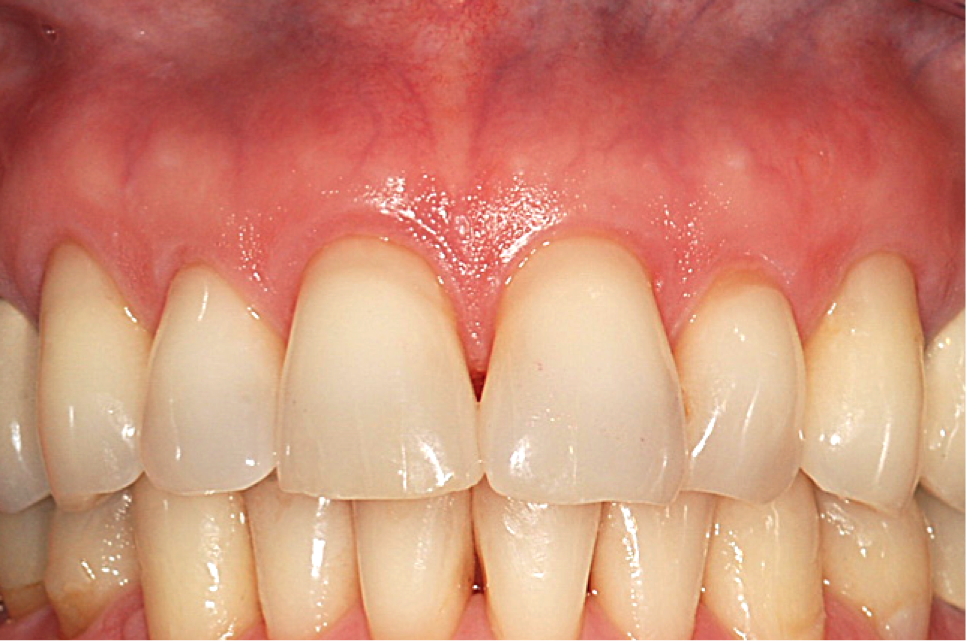

After 1 week, rapid healing and good closure were observed. After 2 years, complete root coverage was visible, a thicker alveolar housing was achieved, and the gingiva was more resistant to future breakdown (Figure 12).